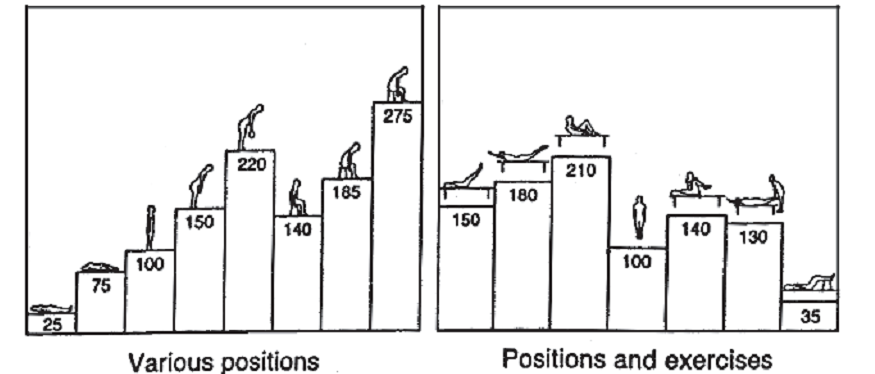

Hình 2: Sự thay đối tương đối áp lực nội đĩa đệm (L3) ở các tư thế và vận động khác nhau (áp lực khi đứng thẳng là 100%). (theo Nachemson, 2000).

- Bất động.

Là biện pháp cần thiết trong điều trị đau thắt lưng cấp và thoát vị đĩa đệm nặng. Nằm bất động tương đối trên phản cứng, ở tư thế ngửa, 2 chân hơi co ở khớp gối và khớp háng để chùng cơ và giảm áp lực nội đĩa đệm (có thể cho gối tròn đệm vào vùng khoeo). Đeo đai thắt lưng là một biện pháp bảo vệ cột sống tốt trong giai đoạn đau nhiều.

Kéo giãn cột sống là tác động cơ học vào vùng kéo nhằm làm mở rộng khoang gian đốt (với trọng lực 30-40kg, sau 20 phút, có thể kéo rộng 1-1,5mm), khôi phục lại cân bằng lực cơ của các hệ thống dây chằng. Ngoài ra còn có tác dụng lâm sàng giảm đau (do giãn cơ, giảm áp lực nội đĩa đệm, giải phóng chèn ép thần kinh). Tăng dần vận động của cột sống, khôi phục vị trí đĩa đệm, giảm các di chứng (mất đường cong sinh lý, lệch vẹo cột sống…).